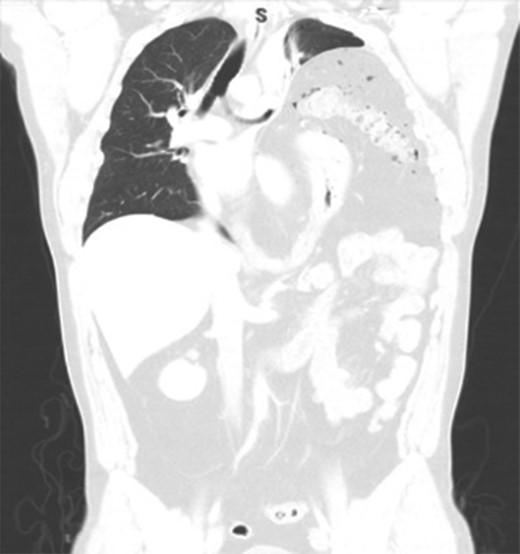

Two days later, the patient re-presented to the emergency department with left-sided pleuritic chest pain. The heart rate was 92 beats/min and the respiratory rate was 23 breaths/min on room air. The patient was stable, looked well, and his pain resolved almost entirely at time of examination. Clinically relevant labs showed a WBC of 8 × 109/L (normal range: 4–11 × 109/L). The CT did not show any significant enlargement of pneumoperitoneum; however, significant rightward shift of the mediastinum was noted. So we suggested worsening tension in the left hemithorax with further collapse of the left lung (Fig. 3). Despite being clinically stable, the mediastinal shift which was not present on the previous admission was concerning and thus the patient was taken to the operating room with the decision to repair the hernia. A left thoracotomy was used to enter the chest cavity. There was severe atelectasis of upper and lower lobes. We immediately noted a large hernia sac which encompassed the entire chest cavity and the remaining diaphragmatic muscle was significantly thinned out. The hernia sac was opened in order to identify the source of the pneumoperitoneum seen on imaging which we had suspected to be of gastric origin. Upon examination of the abdominal contents which required meticulous dissection off the herniated diaphragm from chronic adhesions, we were able to identify a well-developed perforated gastric ulcer on the anterior surface of the greater curvature of the stomach (Fig. 4). This ulcer was resected with a wedge GIA stapler and the hernia was subsequently closed by bringing the muscles together and imbricating the closure with the redundant sac using prolene sutures. Upon closure, we did not place a mesh due to the possible contamination from the gastric perforation. When the repair was complete and the patient taken off the one-lung ventilation, his lungs immediately pinked up and re-expanded. Overall, the patient tolerated the procedure very well without any post-operative complication. Two days later, we carried out an upper GI series which showed no evidence of any extravasation and his diet was advanced. On the sixth post-operative day, the patient was discharged home. He was re-evaluated in clinic 2 weeks later and continued to progress well with a stable repeat chest x-ray (Fig. 5).